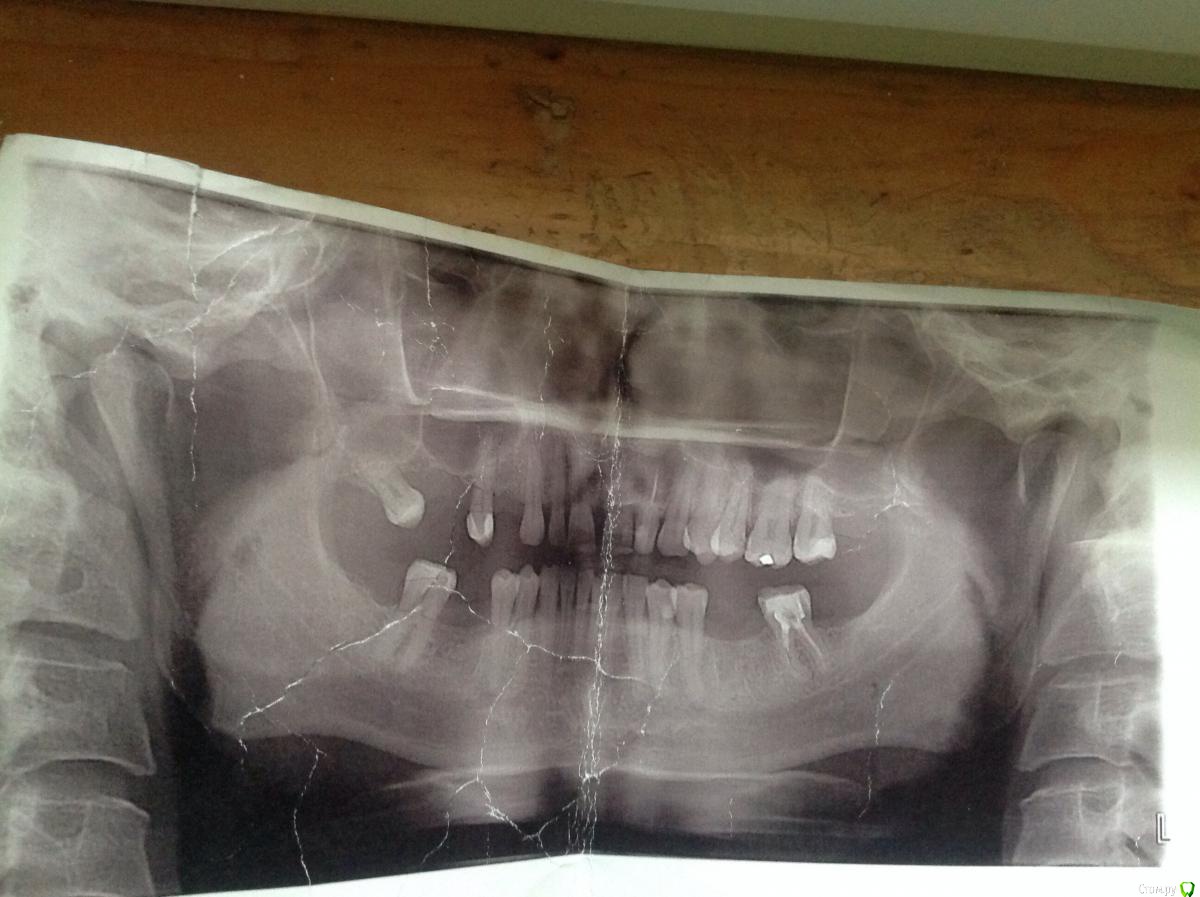

Итак. Был на консультациях имплантологов, ортопедов, ортодонтов. Все говорят по разному: кто-то прям сейчас готов имплантировать, кому то не нравится прикус(глубокий, дистальный)

1. критична ли моя ситуация для выкручивания имплантов по прикусу или нет? (не "полетят" ли они через три-пять лет активного жевания?)

Извиняюсь за качество Ортопантограммы, немного помялась.

дополнительно по внчс. захрустел слева год назад. уйдут ли с ним проблемы после имплантации/брекетов?

Ортопедически поднять прикус можно, такие методики были раньше, но Вам нуджно ортодонтическое лечение. "Поднять" прикус и поставить боковые зубы ровнее - важно для протезирования в последущем. Носить съемные протезы, замещающие промежутки, образованные отсутствующим зубами не получится- зубы будут двигаться.